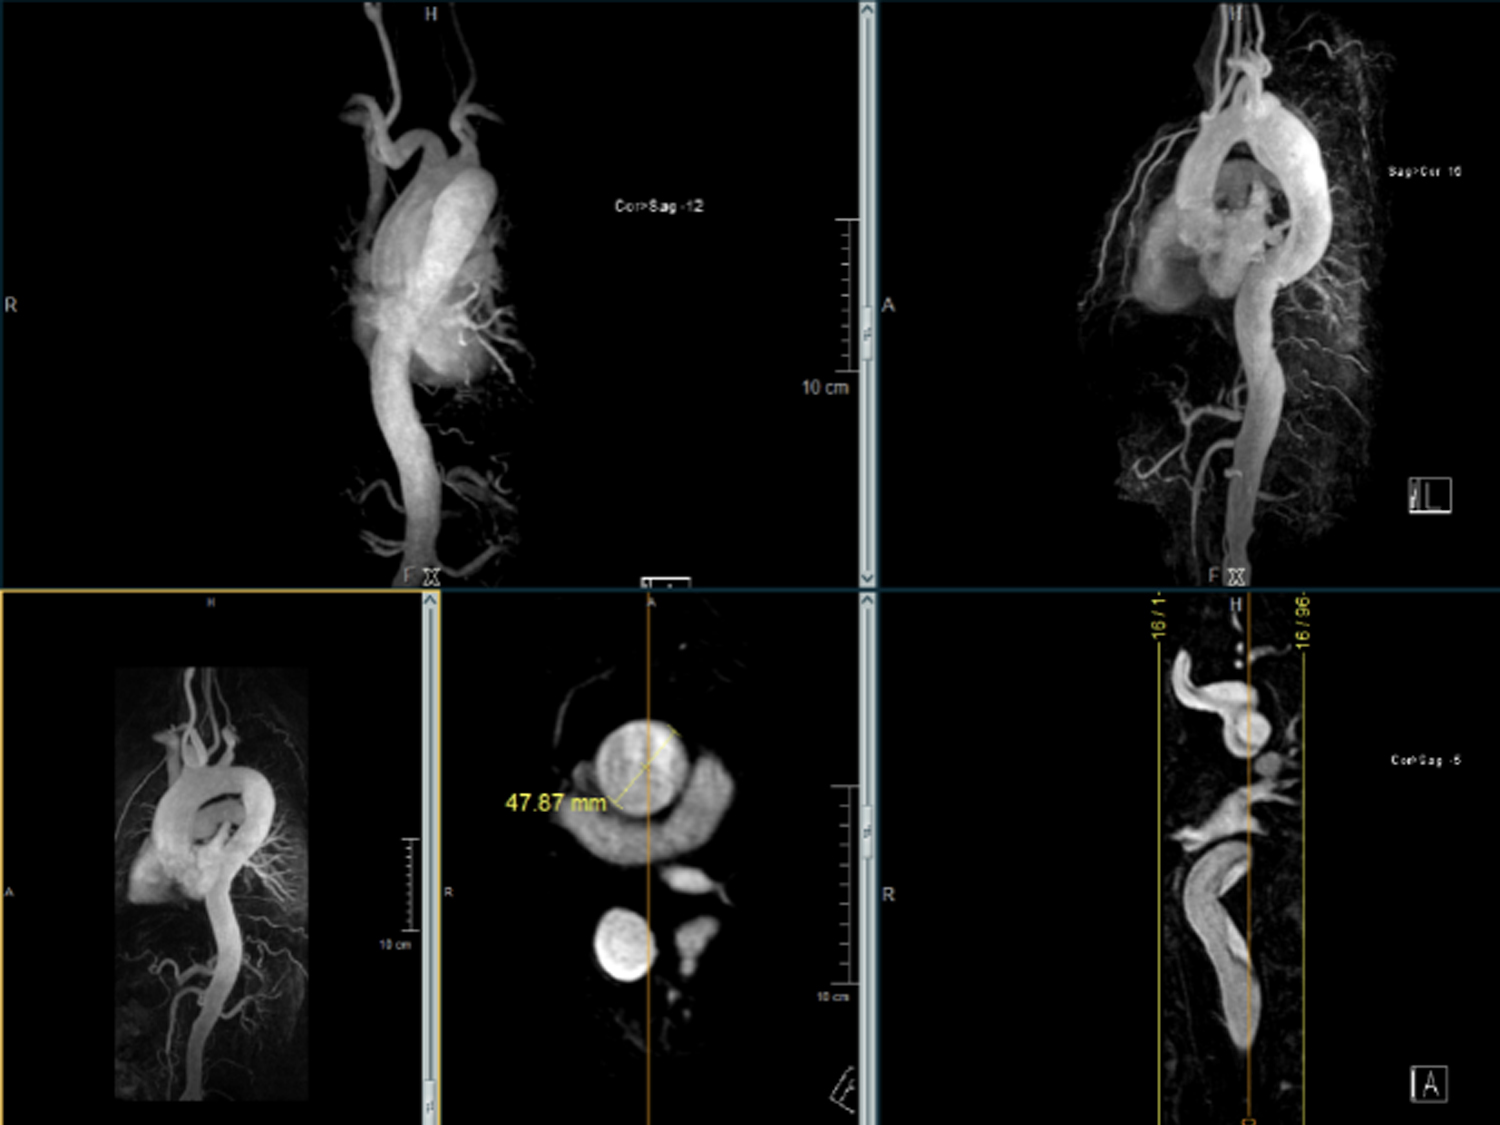

„MRT“ steht für Magnet­resonanz­tomographie, auch bekannt als Kernspin­tomographie. Es ist ein bildgebendes Verfahren, das Magnetfelder und Radiowellen verwendet, um detaillierte Schnittbilder des Körpers zu erzeugen.

Im Gegensatz zu Röntgenstrahlen oder CT-Scans, die ionisierende Strahlung verwenden, nutzt die MRT starke Magnetfelder und Radiowellen, um Bilder zu erzeugen. Dies macht die MRT zu einem besonders sicheren Verfahren für die Diagnose vieler Erkrankungen und Verletzungen, insbesondere im Bereich der Weichteile wie Gehirn, Rückenmark, Gelenke, Muskeln und Organe.